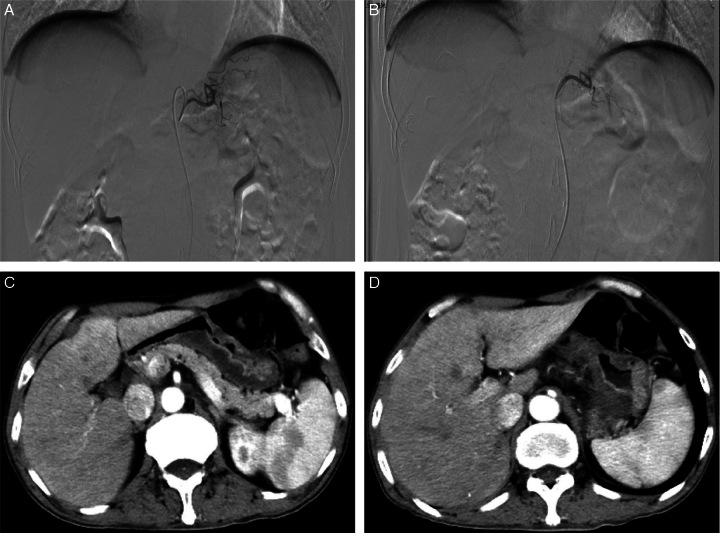

Gastric cancer is the most common type of gastrointestinal cancer in China which about 80% of patients are locally advanced or advanced when diagnosed. Surgery along brings high recurrence rate for locally advanced gastric cancer (LAGC), and neoadjuvant therapies are needed. The use of programmed cell death-1 (PD-1)/programmed death-ligand 1 inhibitor nowadays improved the disease-free survival for LAGC, however, only <35% of patients achieved pathologic complete response (pCR) after neoadjuvant therapy nowadays. Therefore, new regimens are needed to be investigated. Gastric artery chemoembolization is applied to metastasis gastric cancer and researches showed interventional therapy can enhance the antitumor effect of PD-1 inhibitor. Here, for the first time, we combined gastric artery chemoembolization with tislelizumab (a PD-1 inhibitor) for neoadjuvant therapy of a patient with LAGC. The patient achieved pCR after a D2 resection and tumor regression grade score was 1. After surgery, the patient received tislelizumab 200 mg per 3 weeks, and showed no sign of recurrence after 6 months of follow-up. The study indicated the use of tislelizumab and gastric artery chemoembolization for neoadjuvant therapy may bring a better pCR rate and prognosis of LAGC.